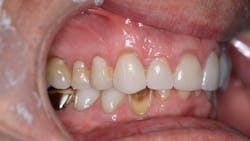

Radiographically, the first thing I noticed were the tabletopped occlusal surfaces (figures 1 and 2). Clinically, the same was evident, along with generalized wear facets on the posterior teeth (figures 3 and 4). The bite was deep (figures 5 and 6), and the lower anterior teeth had been worn down to half their original size. There were new ceramic crowns on nos. 21, 28, and 29. I also noted that there was an occlusal stop/resin on no. 13, but there was no significant effect on his occlusion as it was even on the right and left sides.